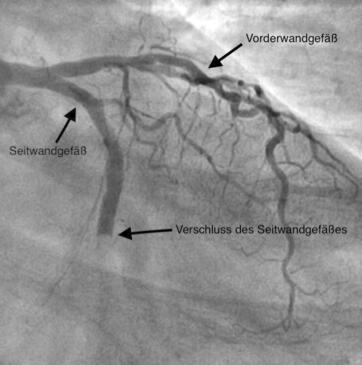

Bei der Linksherzkatheteruntersuchung werden neben der Darstellung der linken Herzkammer (Ventrikulographie) die Herzkranzgefäße mittels Röntgenkontrastmittels (Koronarangiographie) sichtbar gemacht. Die Linksherzkatheteruntersuchung wird in der Regel durch Punktion des rechten/linken Leistengefäßes durchgeführt, kann aber auch durch Punktion des Gefäßes am Handgelenk bzw. an der Ellenbeuge vorgenommen werden. Mit der Linksherzkatheteruntersuchung können Einengungen bzw. Verschlüsse des Herzkranzgefäßes, die Pumpfunktion der linken Herzkammer und der Schweregrad der Herzklappenfehler (Undichtigkeit/Einengung) beurteilt werden.

Die Koronarangiographie (Darstellung des Herzkranzgefäßes mittels Röntgenkontrastmittels) führt zum Nachweis von Einengungen, Verkalkungen und Verschlüssen der Herzkranzgefäße. Sie ist eine wichtige Voraussetzung, um zu entscheiden, ob eine medikamentöse Therapie, eine Ballonaufdehnung (PTCA) oder eine Bypassoperation sinnvoll ist. Im Falle einer Einengung des Herzkranzgefäßes kann diese in der gleichen Sitzung mit Ballonaufdehnung (PTCA/PCI) und Stent (Gefäßstütze) behandelt werden.

Die früher verwendeten konventionellen Metallstents bilden heutzutage eine große Ausnahme und werden nur in speziellen Fällen implantiert. Die überwiegende Mehrheit aller Stents sind medikamentenbeschichtete Stents, die eine überschießende Proliferation von Zellen, welche zu einer Wiederverengung des Gefäßes führen würden, hemmt.